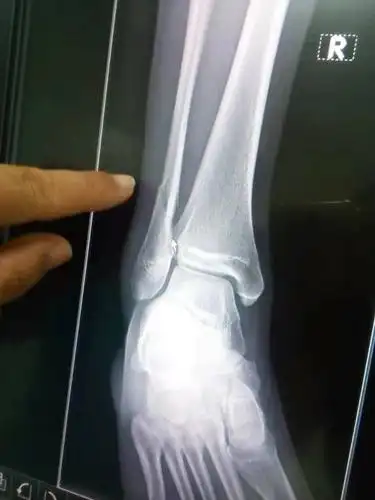

三例胫腓骨远端骨折